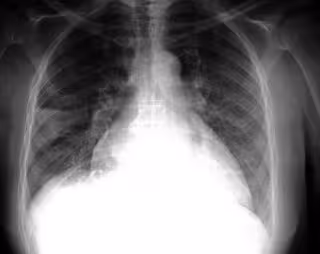

Patología pulmonar

FLICKR/PULMONARY PATHOLOGY/CC BY-SA 2.0